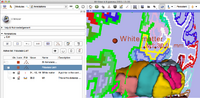

Label Statistics with charting and visualization